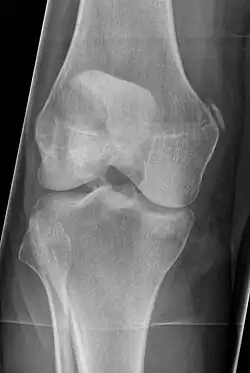

| Pellegrini-Stieda syndrome. Also visible is a fracture of the patella. |

Pellegrini–Stieda syndrome (also called Stieda disease and Köhler–Pellegrini–Stieda disease) is the ossification of the superior part of the medial collateral ligament of the knee. It is a common incidental finding on knee radiographs. It is named for the Italian surgeon A. Pellegrini (b. 1877) and the German surgeon A. Stieda (1869–1945).[1] While the eponym refers to Pellegrini and Stieda, the condition was first discovered by Köhler in 1903, before any namesakes. Pellegrini-Stieda combines the aforementioned radiographic findings and concomitant medial knee joint pain or restricted range of motion.[2]

Diagnosis is typically made on radiographs demonstrating the Pellegrini-Stieda syndrome sign accompanied by pain or restriction of range-of-motion of the knee joint.[2] Pellegrini-Stieda syndrome sign is typically described by a longitudinally linear opacity, which is a process that is describes characteristic of calcification in the soft tissue located medial to the medial femoral condyle.[2] This calcification seen on imaging represents the ossification of the medial collateral ligament, which typically does not develop until approximately three weeks after the initial injury.[2]It is important to note to distinguish this radiographic finding from that of a medial femoral condyle avulsion fracture, which is an injury in which a pulling force of a tendon or ligament fractures away a piece of the bone from its attachment site.[2]